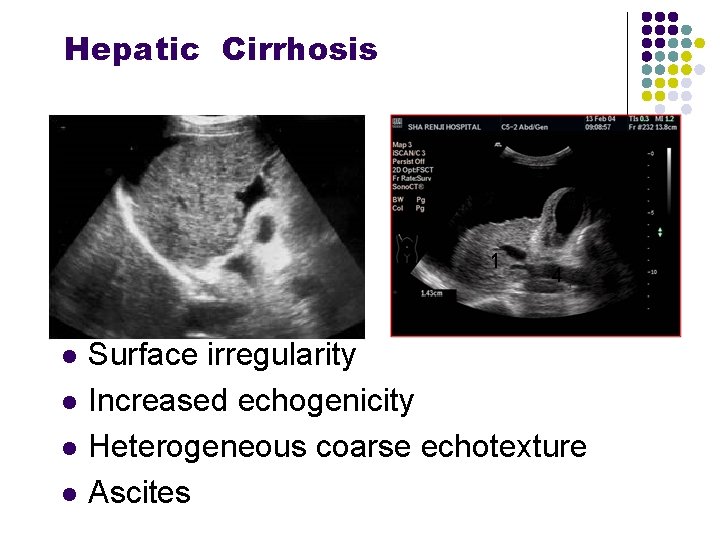

Hepatic Cirrhosis l l Surface irregularity Increased echogenicity Heterogeneous coarse echotexture Ascites

Heterogeneous coarse echotexture Surface irregularity Ascites Decreased definition of walls of portal venules

Heterogeneous coarse echotexture Surface irregularity Ascites Decreased definition of walls of portal venules